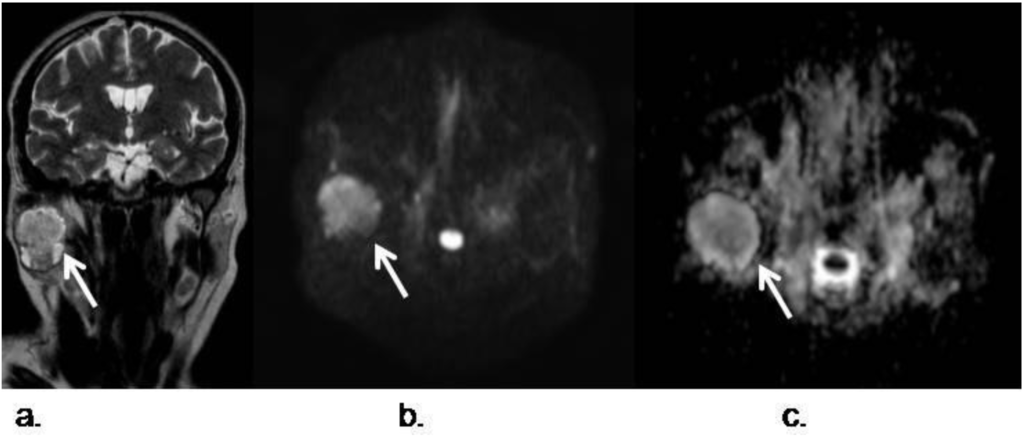

- Razek, A.; Gaballa, G.; Elhawarey, G.; Megahed, A.S.; Hafez, M.; Nada, N. Characterization of pediatric head and neck masses with diffusion-weitghed MR imaging. Eur. Radiol. 2009, 19, 201–208. [Google Scholar] [CrossRef]

- Freling, N.J.; Merks, J.H.; Saeed, P.; Balm, A.J.; Bras, J.; Pieters, B.R.; Adam, J.A.; van Rijn, R.R. Imaging findings in craniofacial childhood rhabdomyosarcoma. Pediatr. Radiol. 2010, 40, 1723–1738. [Google Scholar]